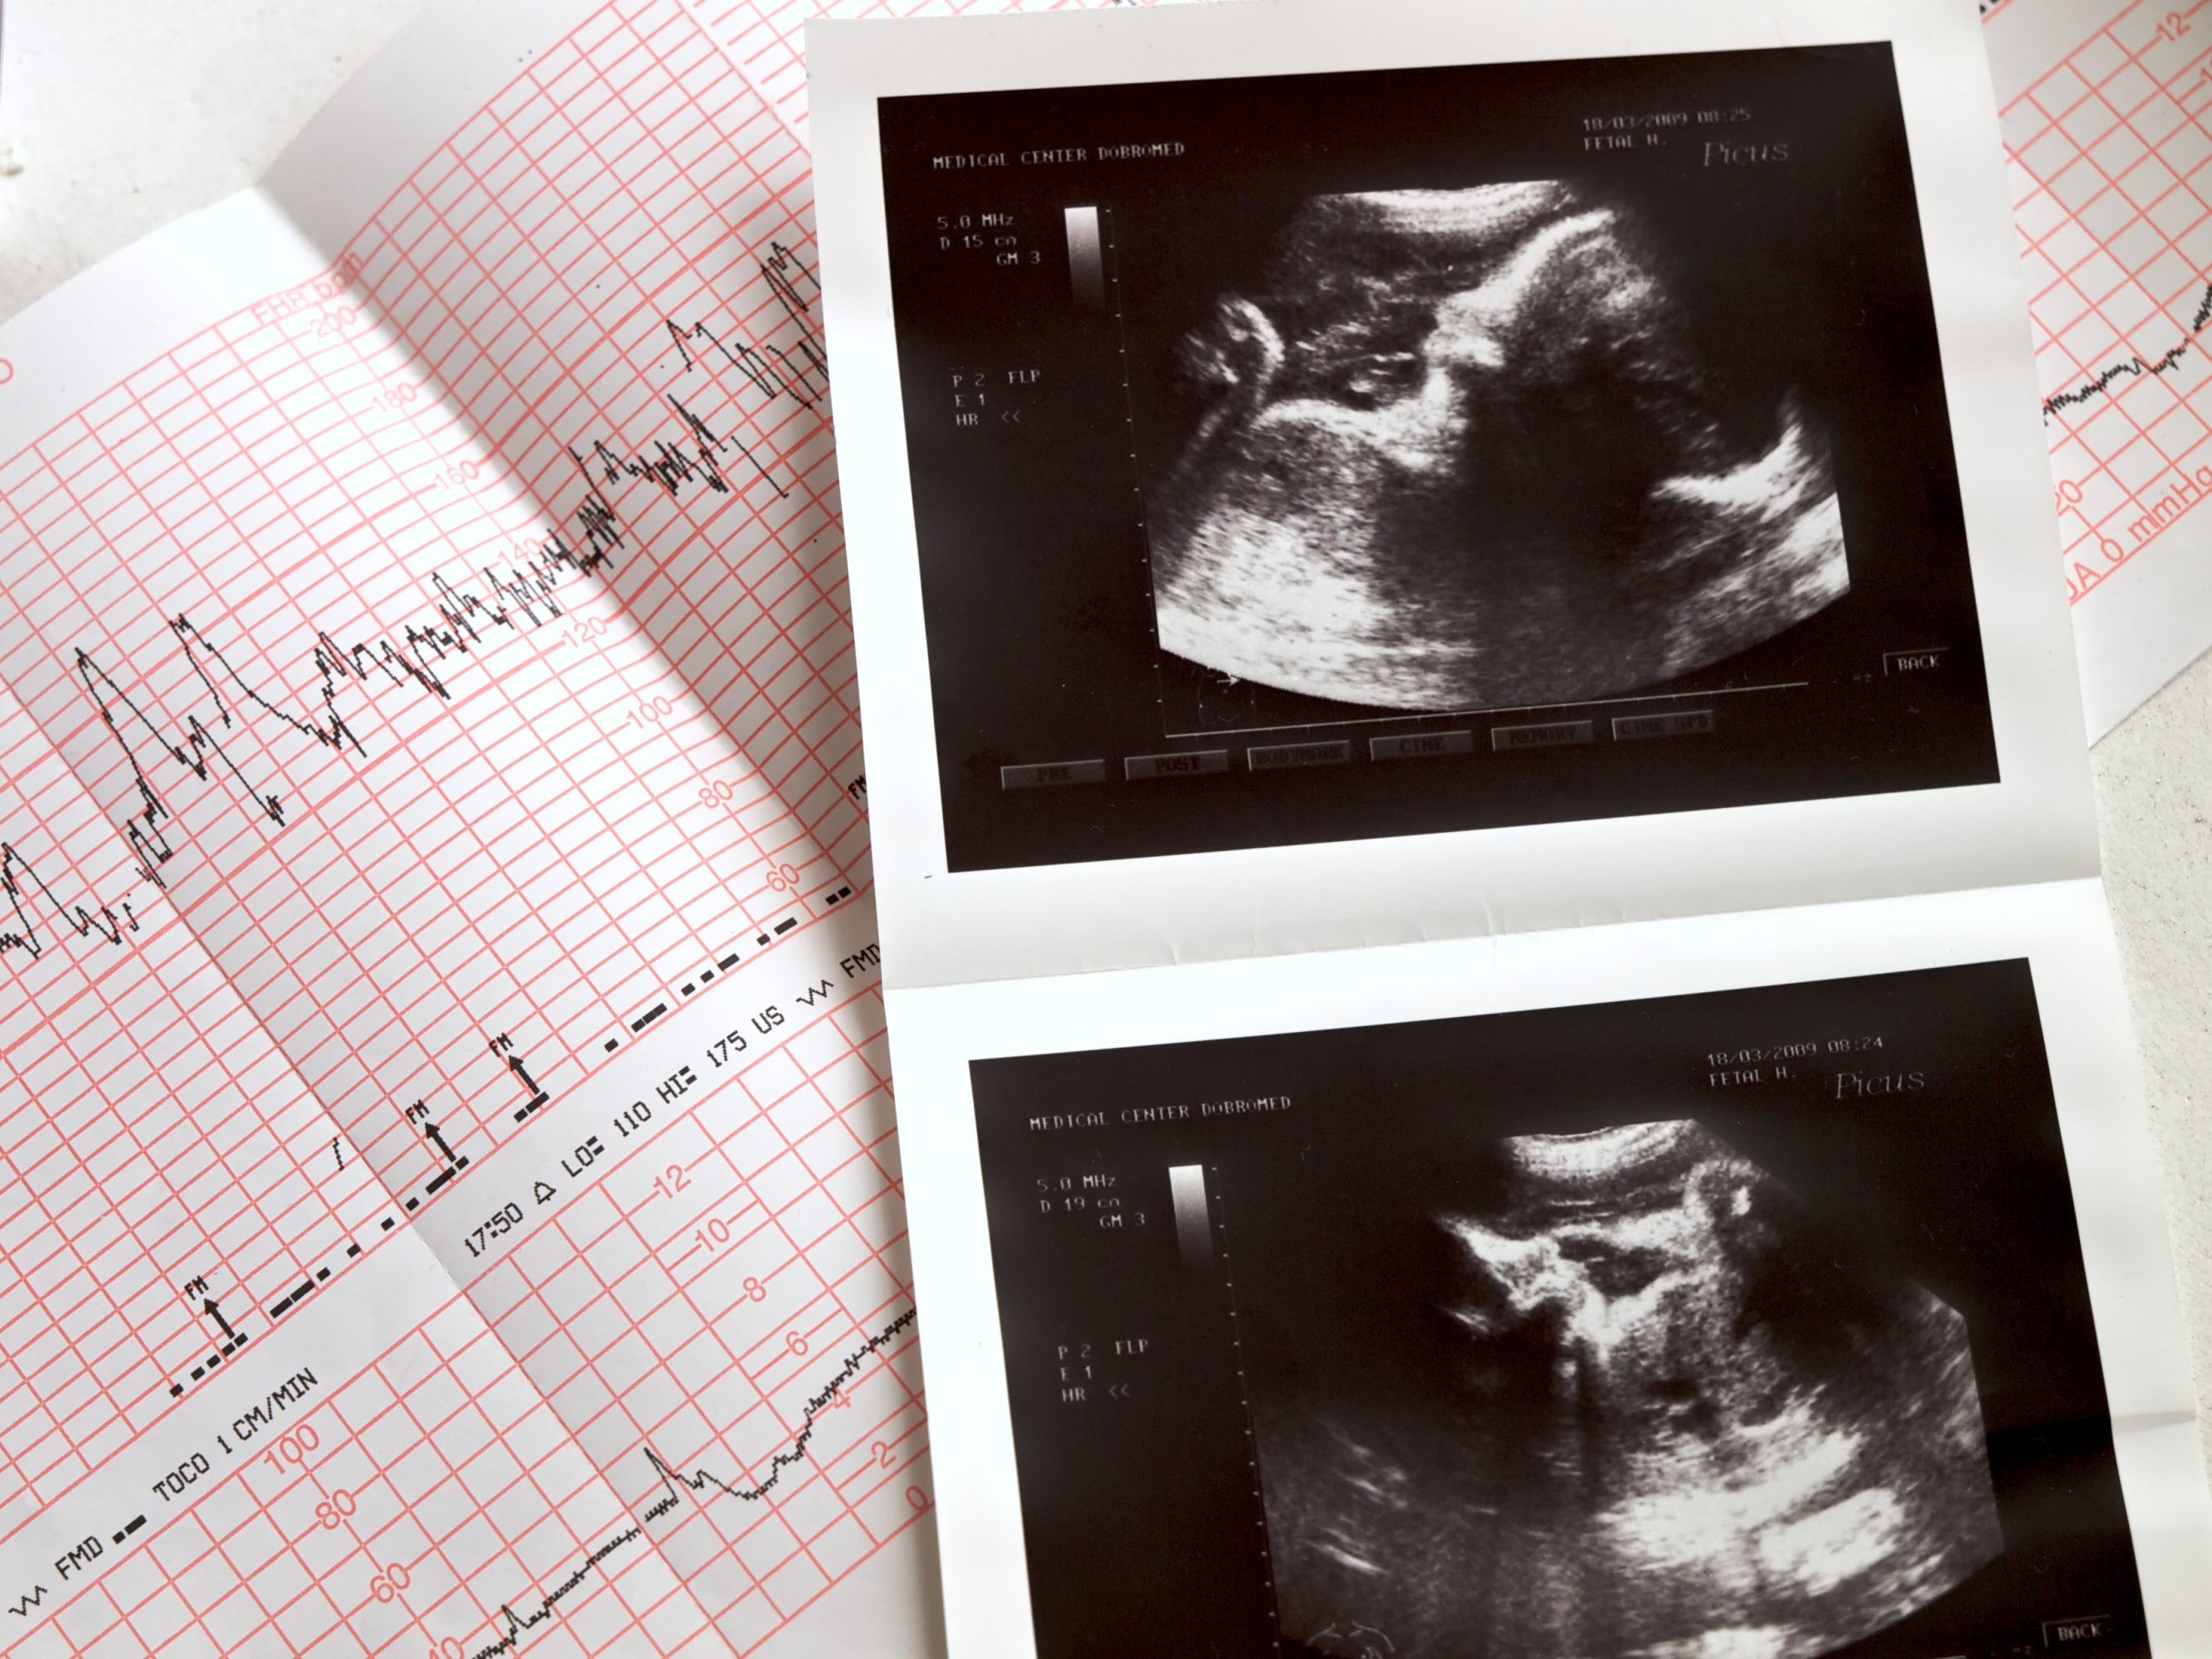

La determinación ecográfica del sexo fetal forma parte de la ecografía morfológica que se realiza entre las 18 y 22 semanas de gestación. Es a partir de estas semanas cuando los genitales del feto están totalmente formados y en una ecografía pueden distinguirse con claridad (a veces, incluso antes, entorno a la semana 14-16) y los padres pueden saber el sexo del bebé.

Aunque es posible detectar el sexo antes, alrededor de las semanas 14 a 16, la precisión aumenta significativamente después de la semana 18. La ecografía no solo ofrece información sobre el sexo, sino también sobre el desarrollo y bienestar general del feto, lo cual es crucial para un seguimiento adecuado del embarazo.

Es importante tener en cuenta que la determinación del sexo mediante ecografía depende de varios factores, como la posición del feto y la experiencia del profesional que realiza el examen. En algunas ocasiones, la posición del bebé puede dificultar la visualización clara de los genitales, lo que podría retrasar la confirmación del sexo. Por ello, los especialistas suelen recomendar esperar hasta que la ecografía morfológica esté programada para obtener resultados más confiables.

¿Qué vemos en la ecografía?

En la ecografía del primer trimestre hay unos signos ecográficos que nos orientan en la determinación de sexo del bebé. Consiste en la orientación del conocido como tubérculo genital. En función de hacia donde se dirija teniendo en cuenta como referencia la espalda del feto, podemos determinar que el feto es masculino cuando el tubérculo genital con ángulo superior a 30° con respecto a la espalda, o femenino cuando el tubérculo genital es paralelo a la espalda o convergente (ángulo inferior a 30°).

En la ecografía morfológica, la determinación del sexo del bebe se basa en la demostración del pene y el escroto en los fetos masculinos y en fetos femeninos se observa el conocido como «signo del grano de café» que serían los abultamientos de los labios mayores de la vulva. Sin embargo, estos signos no son válidos para la determinación del sexo fetal antes de la semana 14 de gestación.

A veces no se ve con claridad…

En un porcentaje de casos el sexo no se puede ver con claridad por diversos motivos: colocación del feto, obesidad de la madre, escasez de líquido amniótico... Si hay dudas y siempre que el sexo no sea importante para descartar alguna patología relacionada o por antecedente , es mejor no confirmarlo. Si se necesita saber el sexo para descartar algún problema, estaría indicada la realización de un test de DNA fetal o una prueba invasiva.